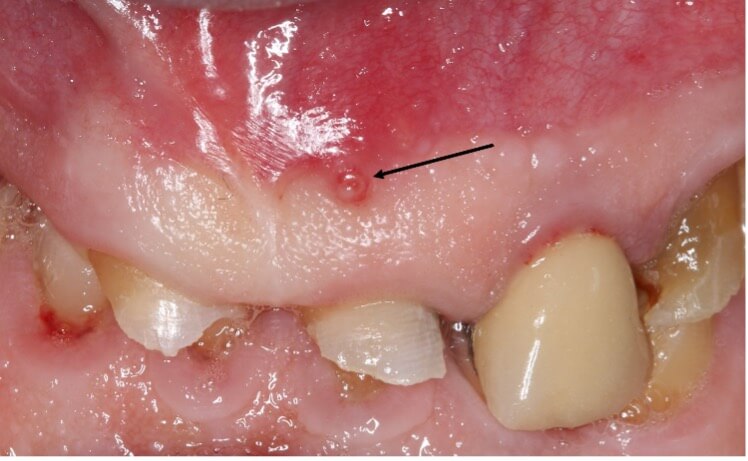

Initially, patients may only experience some warning signs, but the more the infection penetrates into deeper dental layers and towards the pulp (Fig. 2), the more the body’s inflammatory response intensifies, transforming minor discomfort into significant pain. At this stage, called pulpitis, traditional treatments shift from conservative restoration to more invasive procedures like pulp excision and endodontic therapy [25].

Fig. 2.

Intraoral X-ray of tooth #16 before and after carie (*) treatment.